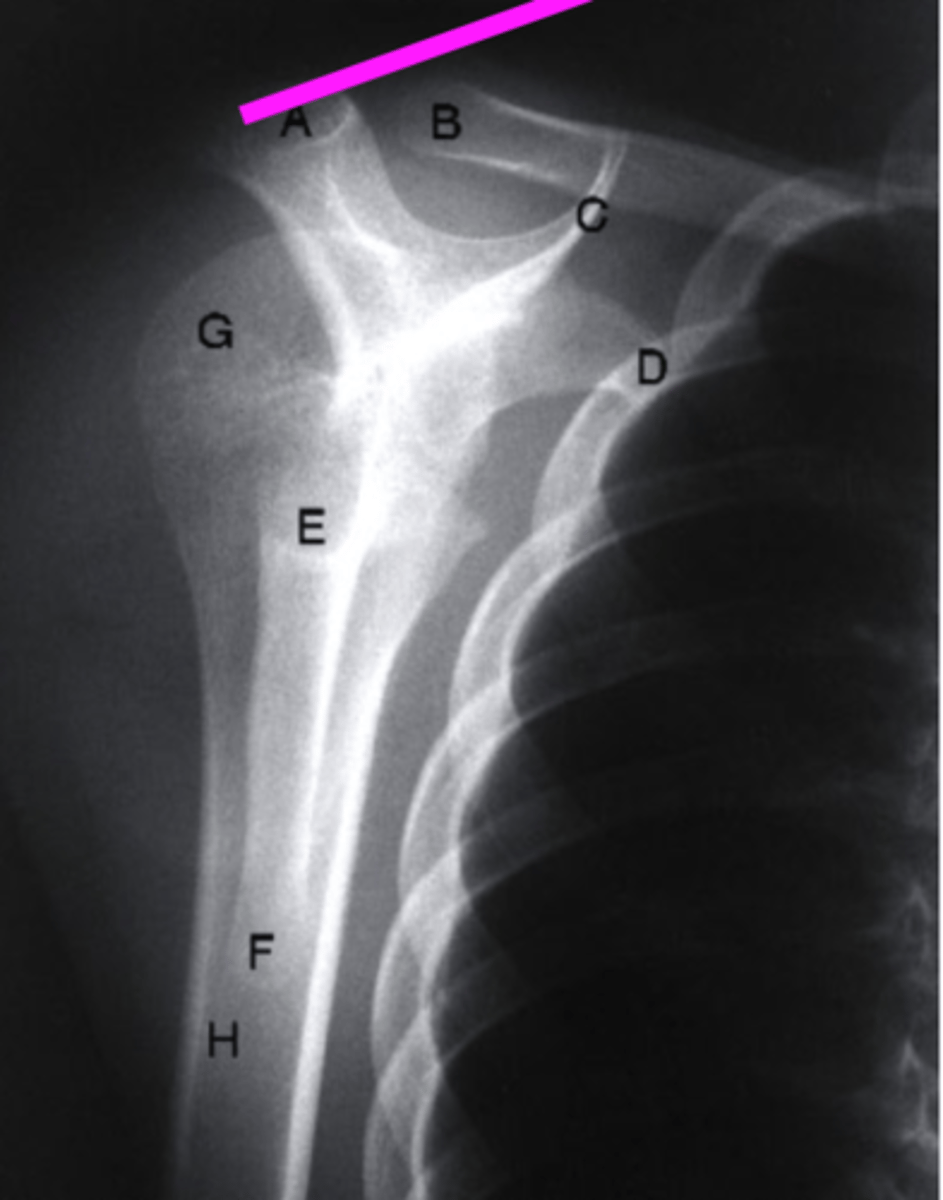

AP + IR

what view is this?

clavicle

what does the pink line point to?

spine of scapula

coracoid process

glenoid fossa of scapula

AC joint

acromion

Humeral Head

lesser tubercle